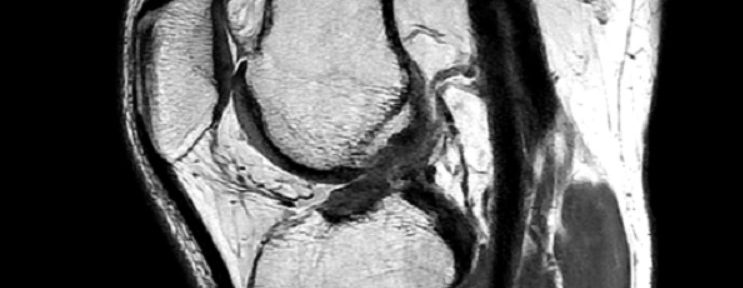

2022 年 2 月 5 日、スキー中に転倒し、右膝を捻った。2 月 10 日に、MRI撮影を行い、診断は次のとおりであった。

2022年2月21日より、当院の前十字靭帯断裂の自然治癒療法をオンラインにて開始した。 6ケ月間、ナチュラリゼーションの運動療法を継続し、2022年8月17日に、再度MRI撮影を行った。

MRIの評価:

前十字靭帯の連続性を確認できる。

8月17日に撮影したMRIを精査すると、完全に明確ではないが、前十字靭帯の連続性が見られる。 この治癒形態は、Iharaの分類ではⅡ型に分類され、Ⅰ型の完全な治癒形態と比較すると、治癒線維は部分的に細いままである。患者は機能的な回復に関しては、非常に良好であり、2022年8月の時点では、日常生活で痛みや不自由を感じていない。患者は、スキーに復帰したいと考えており、今後も、ナチュラリゼーションだけではなく、筋力トレーニングも行っていく予定である。